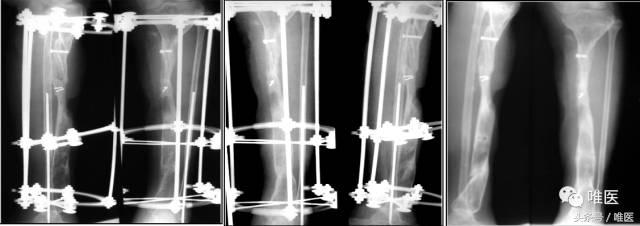

7. 术后随访

二期术后12月:骨缺损完全修复,外架拆除后。

二期术后12月:功能恢复良好

重视断端处理:认真修整断面,使其密实、直接对合。

强调断端间植骨。

必要时改善周围软组织床的血供。

合理的功能锻炼:逐渐积极负重,增加断端间有效应力。